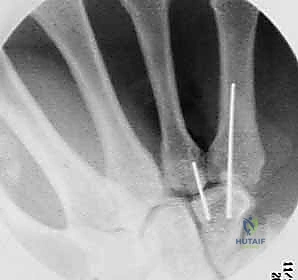

4. التثبيت الداخلي (Internal Fixation)

يتم تثبيت العظام باستخدام أدوات طبية متناهية الصغر مصنوعة من التيتانيوم.

* أسلاك كيرشنر (K-wires): تُستخدم للتثبيت المؤقت أو في الكسور البسيطة.

* المسامير بدون رأس (Headless Compression Screws): تُدفن بالكامل داخل العظم لتجنب احتكاكها بالأوتار، وتوفر ضغطاً ممتازاً لسرعة التئام الكسر.